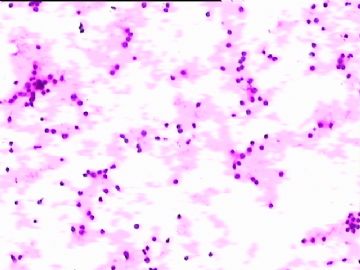

78y,男,胸水。 大家看看那些小于淋巴细胞的东东。

孢子?

图6感觉象是污染的孢子之类的东西。好好回忆一下,制片过程?容器?有没有污染的 可能?

但,最后一图的组织细胞内吞噬现象,怎么解释。

离体的细胞在一定的时间内还是活细胞,所以我推测吞噬细胞可能还是有一定的吞噬功能的。不过,确实也不能就排除了在活体内的微生物感染的可能。结合临床应该能够得到一定程度的澄清。

像是孢子

同意孢子